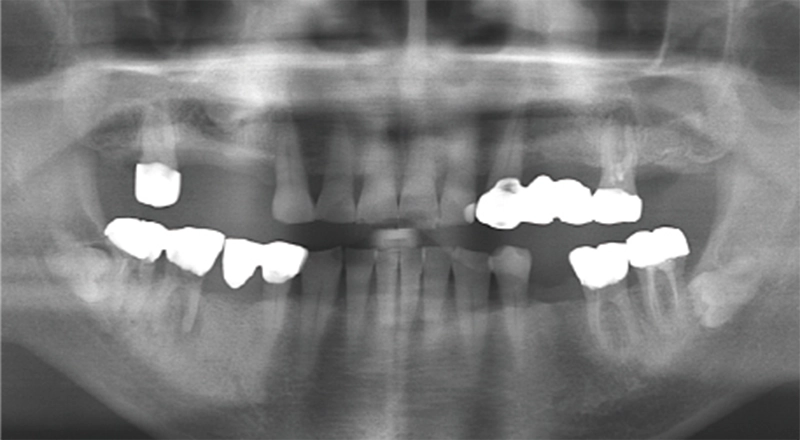

| 主訴 | 噛むと痛い |

|---|---|

| 診断名 | ⻭根破折 |

| 年齢・性別 | 70歳・⼥性 |

| 治療期間・回数 | 8ヶ⽉・6回 |

| 治療方法 | サイナスリフト、インプラント |

| 費用 | 975,700円 |

| 治療上のリスク |

| 主訴 | 歯が抜けている。 入れ歯のところをインプラントしたい |

| 診断名 | 歯の欠損、義歯不適合 |

| 年齢・性別 | 63歳・男性 |

| 治療期間・回数 | 1年3ヶ月・33回 |

| 治療方法 | 精密根管治療、ジルコニアクラウン、GBR、インプラント、ホワイトニング |

| 費用 | 3,949,000円 最高プラン (費用を抑えたプランも提案可能) |